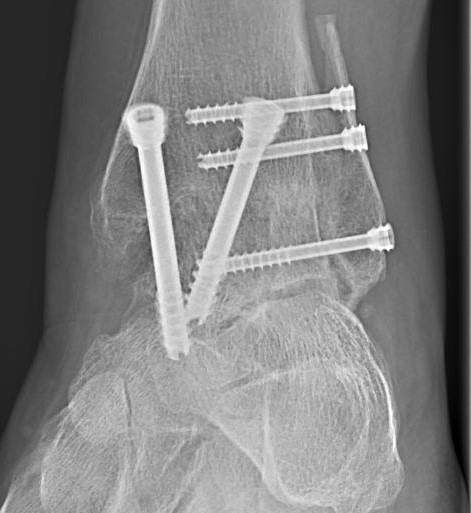

Die Versteifung

Ist das Einbringen eines künstlichen Gelenkes nicht sinnvoll, ist die Versteifung die letzte Therapieoption.

Nach einer Versteifung des oberen Sprunggelenkes ist die Beweglichkeit oft besser als erwartet.

Die Funktion des oberen Sprunggelenkes wird von den Nachbargelenken übernommen. Somit ist die Beweglichkeit des Fußes häufig besser als erwartet und das Gangbild kaum verändert.

Nach Entfernung des Restknorpels wird der Knochen angefrischt und der Fuß in Neutralposition versteift. Die Fixierung erfolgt mit vier Schrauben oder mit einem Arthrodesenagel.

Nach der Operation wird der Fuß in einem Aircastwalker ruhiggestellt und darf zwölf Wochen mit 20 kg teilbelastet werden.